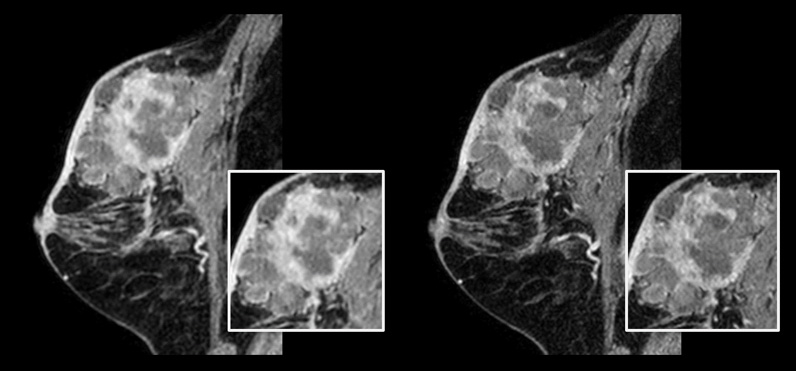

Patient with breast cancer.

On the left: Conventional 3D mDIXON XD scan with 1.0 mm isotropic voxel size in a scan time of 2:22 min

On the right: Compressed SENSE 3D mDIXON XD scan with 0.8 mm isotropic voxel size in a scan time of 2:21 min.

Courtesy: Kurashiki Central Hospital, Okayama. Japan